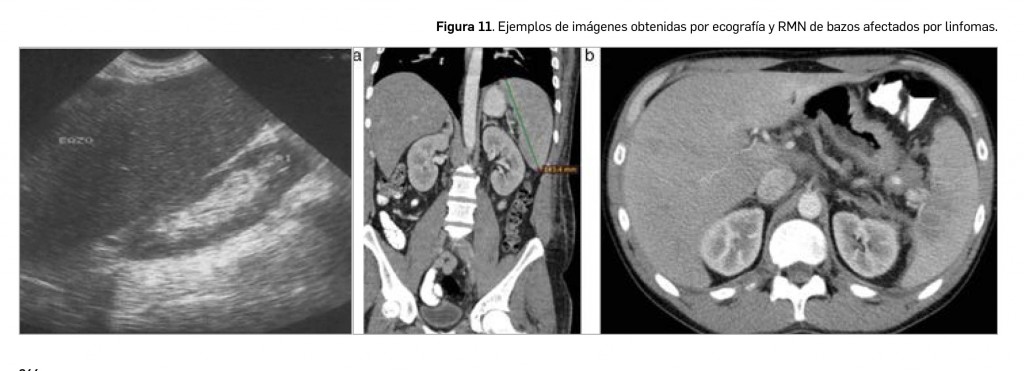

Como segunda causa más frecuente de esplenomegalia, se consideran las enfermedades hematológicas, concretamente linfoma, leucemia mieloide crónica, policitemia vera, hemoglobinopatías, leucemia linfática crónica, mielofibrosis y esferocitosis. Y, en tercer lugar, también puede aparecer un aumento de tamaño esplénico por enfermedades infecciosas, dependiendo del contexto geográfico: la infección por el virus de la inmunodeficiencia humana (VIH), la mononucleosis infecciosa y la leishmaniasis con las más frecuentes en nuestro medio, mientras que, en pacientes procedentes del continente africano, las más prevalentes son la malaria y la esquistosomiasis.